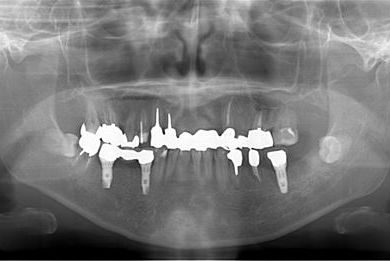

| カテゴリー | 【インプラント治療】【セラミック治療】 | ||||||||||||||||||||||||||||||||

| 性別/年齢 | 女性 / 40歳 | ||||||||||||||||||||||||||||||||

| 主訴 | 右下のブリッジが外れているかもしれないという診断を受けましたが、開けてみないとわからない、場合によっては部分入れ歯と言われ、セカンドオピニオンを希望。腫れがあるのも気になります。 | ||||||||||||||||||||||||||||||||

| 治療方針 | 右下奥、骨再生法によりインプラント治療を可能にする。 | ||||||||||||||||||||||||||||||||

| 治療内容 | インプラント3本(GBR、テンポラリーインプラント+仮歯)、ハイブリッドセラミックブリッジ3本、ハイブリッドセラミッククラウン2本 | ||||||||||||||||||||||||||||||||

| 総治療費 | 1,524,338円 | ||||||||||||||||||||||||||||||||

| 治療期間 | 1年0ヶ月 |